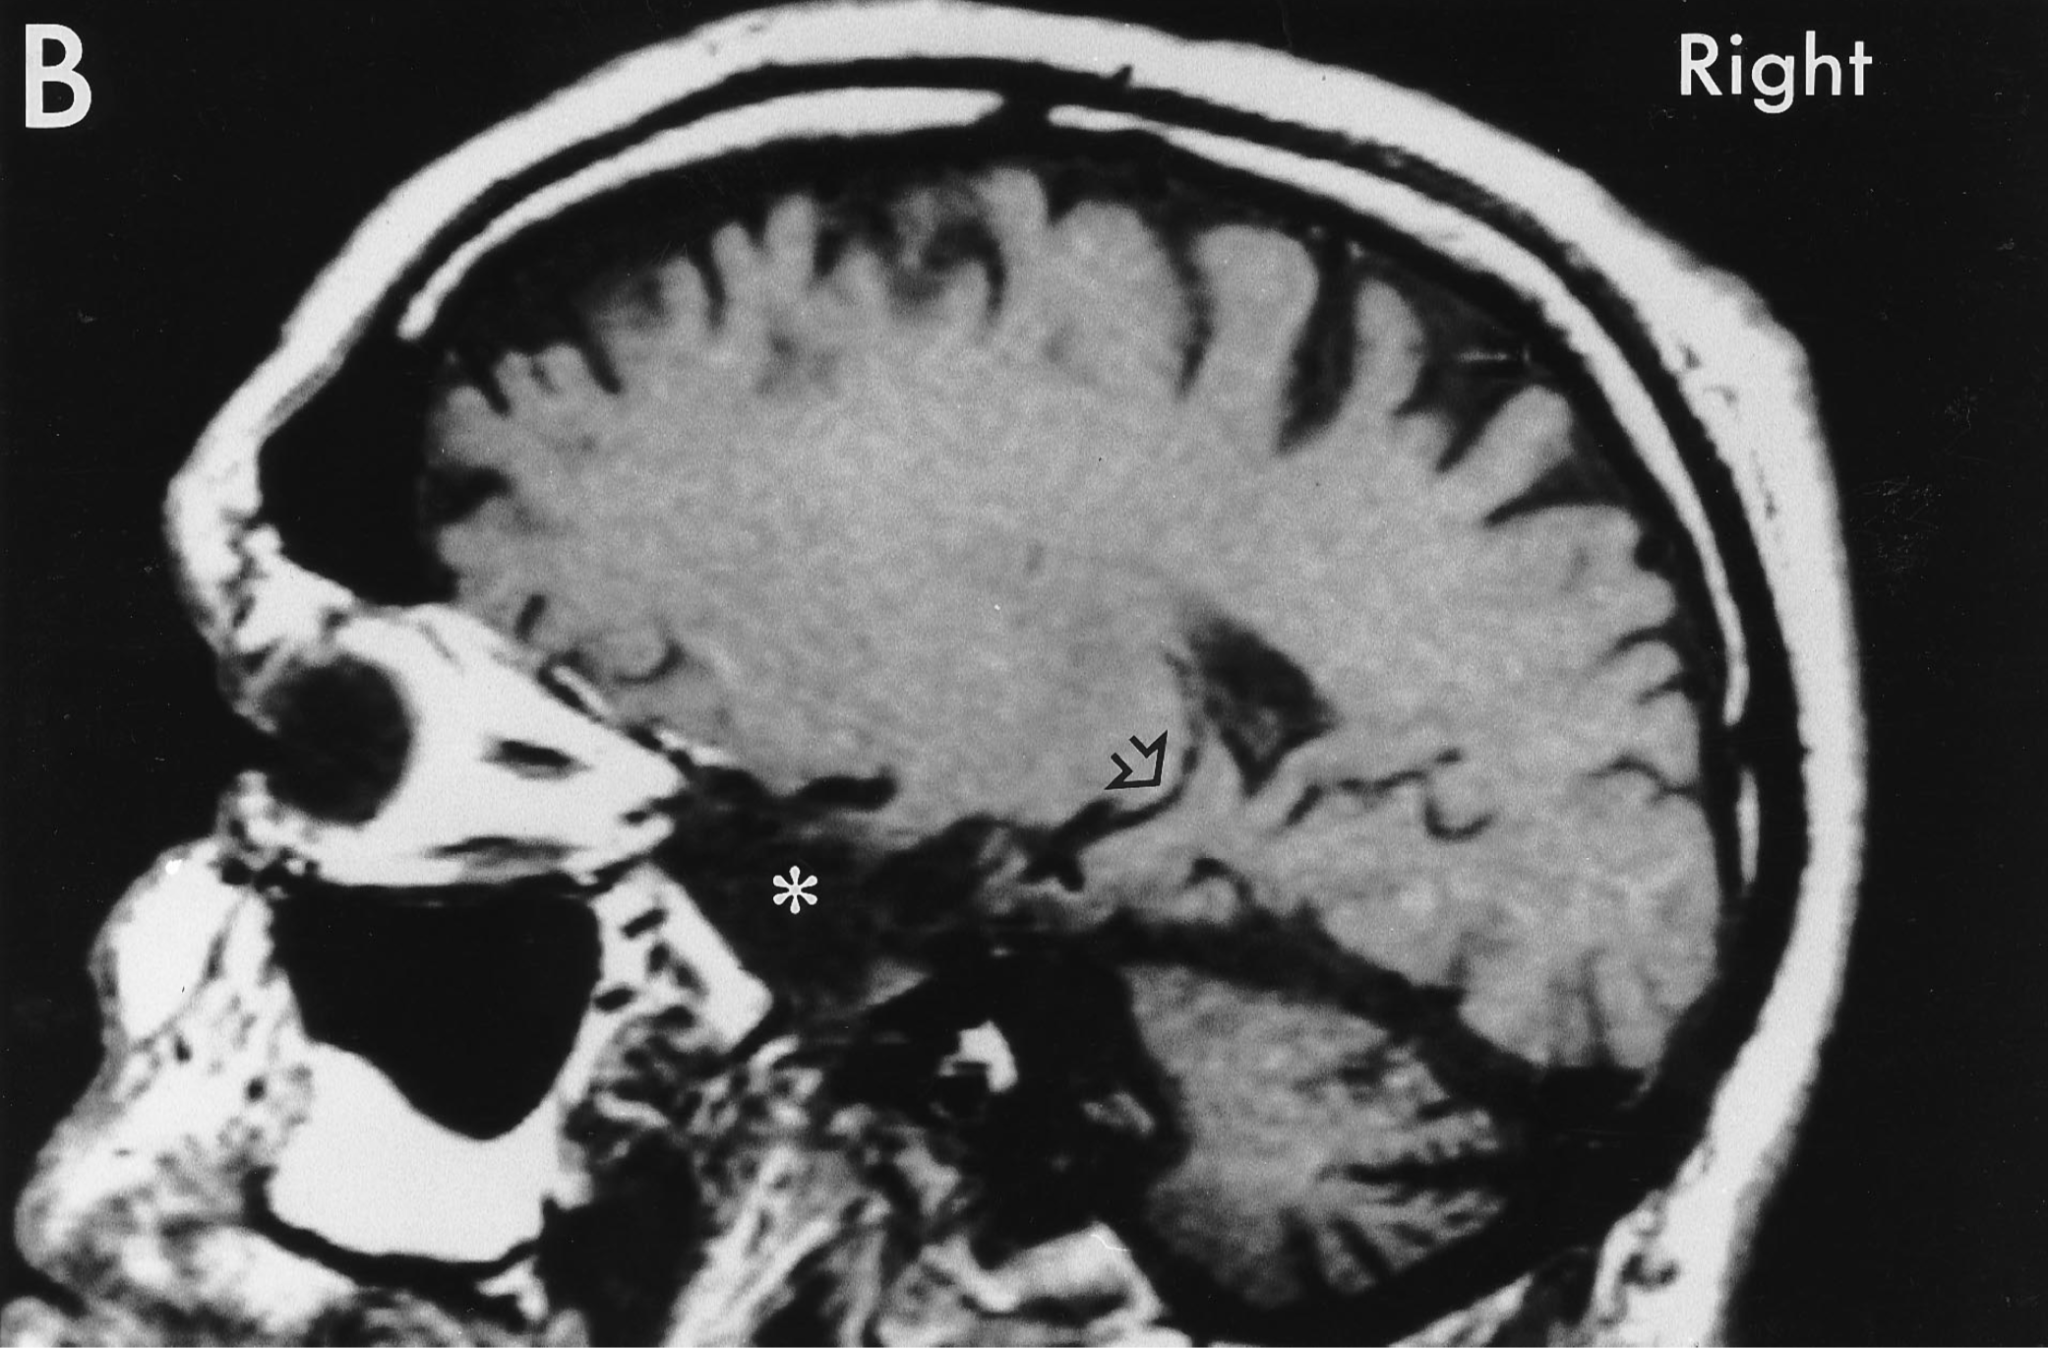

К счастью, Генри Молисон сумел прожить после операции еще очень долго: 55 лет. За это время появились томографические методы исследования. Правда, долгое время проводить МРТ боялись: Сковилль «разметил» операционное поле металлическими клипсами, которые так и остались в мозге Молисона. Врачи опасались, что магнитное поле сместит их, что приведет к повреждению артерий и инсульту. Однако позже КТ показало, что все они весьма далеко от сосудов и вот, в 1992 году Молисону прижизненно сделали МРТ на 1,5-тесловом томографе.

Кое-что разглядеть удалось (вы видите показанные поражения стрелкой), однако полную картину ученые так и не получили. Только после смерти мозг Молисона вновь был подвергнут испытаниям: сначала он, в зафиксированном состоянии был изучен на трёх- и семитесловом томографе, что дало исключительное качество картинки (см. фото внизу), а затем исследователь Джакомо Анезе совершил настоящий научный подвиг: 53 часа резал на микротоме замороженный мозг Молисона на 2401 срез толщиной в 70 микрон каждый. Удивительно, что исследователь «запорол» только два образца. И теперь ученые смогли построить полную карту поражений мозга Молисона.